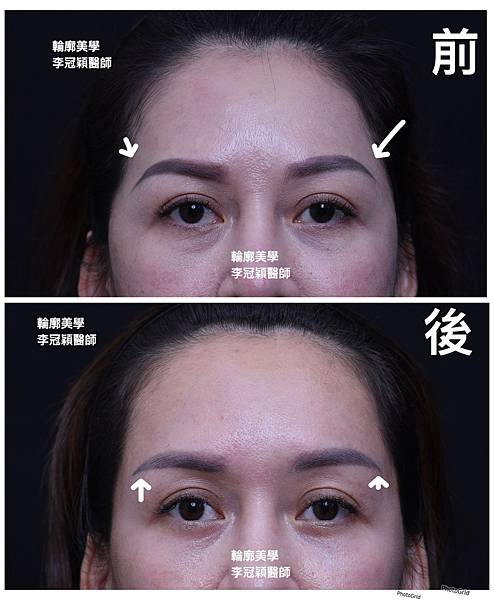

範例:經太陽穴墊片手術,改善臉骨過大比例避免削骨手術。

範例:太陽穴墊片改善臉骨過大比例

太陽穴墊片精準跳調整眉尾角度,改善下垂老態感。同時調整過窄的額型(尖頭型)

可以調節眉尾舒展角度和長度👍

下圖案例:太陽穴墊片精準調整眉尾角度提升,延伸眉尾長度改善下垂老態。

太陽穴墊片調整眉型和眼尾下垂,加強提眉效果和持久度。